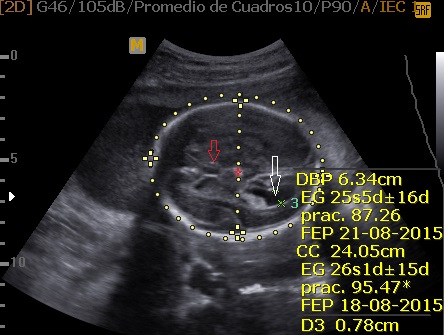

La Neurosonografía Fetal se refiere a la evaluación del Sistema Nervioso Central por Ultrasonidos: cráneo y su contenido (cerebro, ventrículos, tallo, cerebelo, etc.) y de la columna vertebral y su contenido (vértebras, médula espinal, líquido cefalorraquídeo, etc.).

Cráneo

La determinación de la normalidad anatómica depende de la etapa del desarrollo en la que se pretende estudiar en contenido encefálico y del momento de aparición de las anomalías posibles; además, a diferencia de otros órganos cuya estructura madura es bastante estable y resistente a agresiones durante el embarazo, el contenido craneal puede verse afectado en cualquier etapa del embarazo, durante el nacimiento y en vida posnatal.

Las estructuras intracraneales después de la semana 18-20 del embarazo son muy características y permanecen visualmente invariables hasta el final del embarazo, solo modificando sus tamaños a medida que el feto crece. Esto es de gran ayuda ya que permite determinar la aparición de cambios que podrían sugerir desviación de la normalidad y aparición de una malformación congénita o lesión adquirida por eventos externos especialmente relacionados a infecciones y accidentes vasculares fetales.